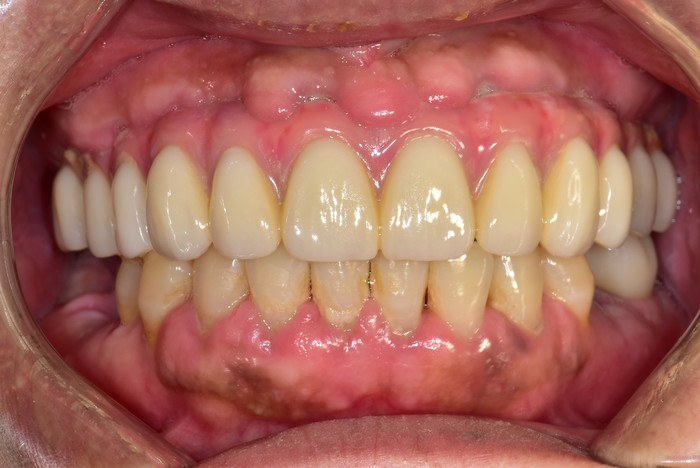

발치를 막고 잇몸을 보호하는

자연치아를 유지하기 위한 마지막 선택

디아트 테라피는

잇몸을 살립니다

자연치아를 지키기 위한 최선의 예방관리. 치아와 잇몸을 동시에 보호하고, 자연치아를 지킬 수 있는 토탈 솔루션입니다.

발치를 막고 잇몸을 보호하는  자연치아를 살리기 위한 마지막 선택

디아트 테라피는 잇몸을 살립니다

자연치아를 지키기 위한 최선의 예방관리.

치아와 잇몸을 동시에 보호하고, 자연치아를 지킬 수 있는 토탈 솔루션입니다.